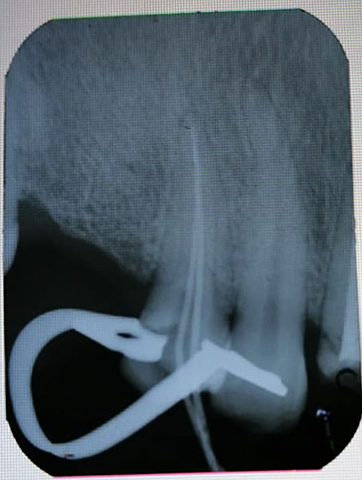

• SERIE RADIOGRAFICA

SERIE RADIOGRAFICA

Se diagnóstica de manera independiente cada organo dentario, para determinar su vitalidad o lesión que pueda padecer, esto se hace con pruebas especificas en el area endodontica. como son prueba de calor, frio o percisión

• FASE ENDODONTICA

FASE ENDODONTICA

Se inicio tratamiento de conductos en los OD. 1.3, 1.6, 2.3, 3.5,3.6 y 4.1 , cabe mencionar que a los OD. 1.3, 2.3 y 3.6 se dejan preparaciones para colocar coronas proviosionales de acrílico, para posteriormente colocar postes y coronas de zirconio libre de metal.